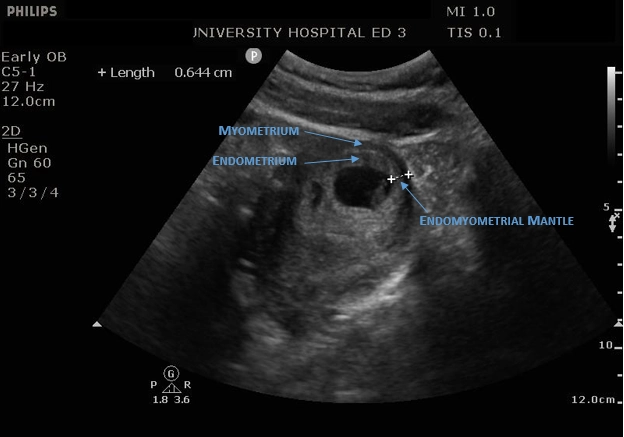

• VI. Thai ngoài tử cung

Thai ngoài tử cung đoạn vòi (Tubal ectopic pregnancy)

Thai ngoài tử cung đoạn kẽ (Interstitial ectopic pregnancy)

Thai bám sẹo mổ lấy thai (Cesarean section scar pregnancy)

Thai ở cổ tử cung (Cervical pregnancy)

Thai ngoài tử cung ở buồng trứng (Ovarian ectopic pregnancy)

Song thai hỗn hợp (Heterotopic pregnancy)

Thai ngoài tử cung trong ổ bụng